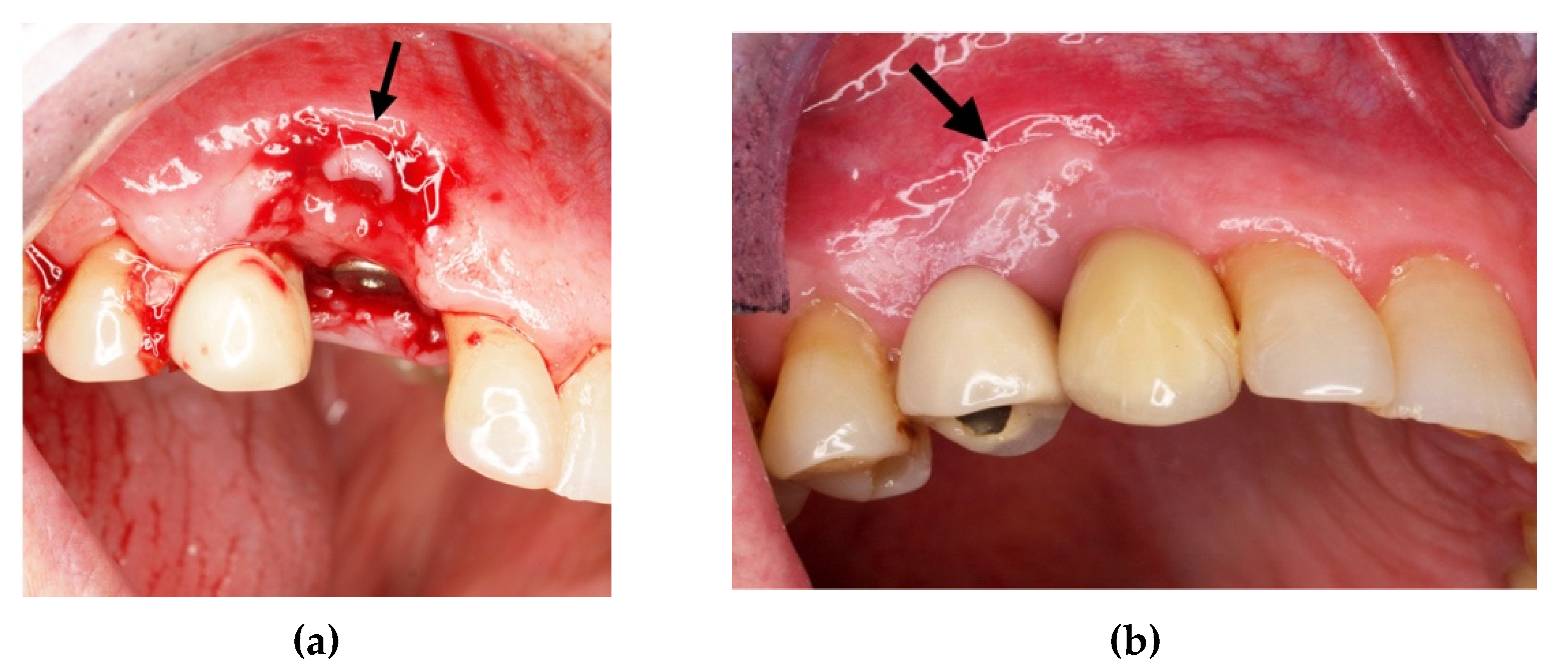

The titanium barrier was removed and the growth of new bone tissue, even if not completely mature, was observed (Figure 9a). After a further 6 months, we noted how pre-existing keratinized gingiva of keratinized mucosa indicated by the arrow in Figure 9a, contributed to the formation of the adherent gingiva band as shown in Figure 9b.

Figure 9.

(a) Flap of keratinized mucosa indicated by the arrow; (b) finalization with a prosthetic crown.

The surgery protocol was the same as described in the previous case (Figure 11a–e). The extraction of teeth and the simultaneous insertion of the implants was performed in the same session (Figure 11a). The enriched clot (1 g beta-tricalcium phosphate for every 5 mL of clot) was protected by the shaped foil fixed with screws (Figure 11b) and its successive removal was at six months (Figure 11c). A further six months were necessary for soft tissue maturation (Figure 11d,e). In this case, the flap of keratinized mucosa, indicated by the white arrow in Figure 11c–e, contributed to the stability of the keratinized mucosa. At the follow-up, the gingival tissue was adequately matured, avoiding further graft of soft tissue (Figure 12).

Figure 11.

(a) Avulsion of the teeth and simultaneous insertion of the implants; (b) Use of the enriched clot and cover with the foil blocked with the screws; (c) Removal of the foil at six months; (d) Maturation of the tissues after one week from the withdrawal of the foil; (e) pre-prosthetic situation of implants and mucosa.